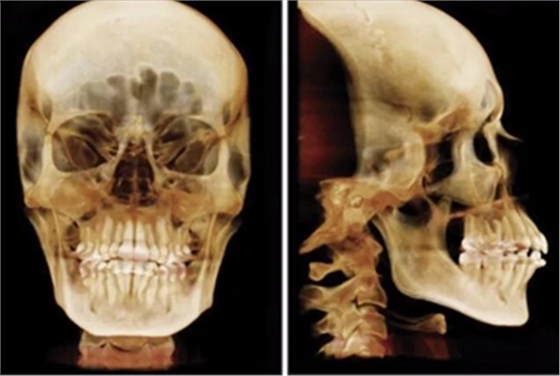

患者曾行正畸治療,現(xiàn)覺(jué)笑容不美觀前來(lái)就診。患者正面觀及側(cè)貌示下頜發(fā)育不足,偏高角,唇閉合不全。上下頜中線齊。覆合、覆蓋4毫米。磨牙關(guān)系及尖牙關(guān)系II類(lèi)。上頜擁擠度4mm,下頜擁擠度6mm。4顆第一前磨牙在第一次正畸治療時(shí)已拔除。上下牙弓呈尖圓型,牙弓狹窄。

頭影測(cè)量分析,SNA角84°,ANB角6°,高角型,詳見(jiàn)下表。